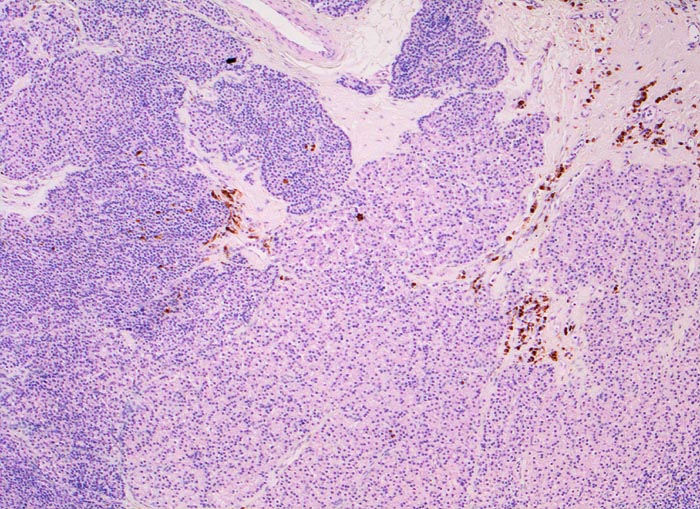

Für die Diagnose wird der Kalzium- und Phosphatspiegel bestimmt. Außerdem Parathormon-, Serumphosphatase- und Vitamin-D Spiegel. Neben den Laboruntersuchungen müssen Betroffene auch geröngt werden zum Nachweis der renalen Osteopathie. Nebenschilddrüsen sind makroskopisch nicht immer eindeutig von kleinen Lymphknoten oder Schilddrüsenknoten abzugrenzen. Deshalb werden operativ entnommene Nebenschilddrüsen zur Bestätigung der Organdiagnose oftmals mittels intraoperativem Schnellschnitt untersucht. Auch eine Unterscheidung von Schilddrüsengewebe und Nebenschilddrüsengewebe kann die Indikation für eine intraoperative Schnellschnittuntersuchung sein (> 4334).

• Knotige vergrösserte Nebenschilddrüse. Abgrenzung der einzelnen Knoten durch breite Fibrosebänder.